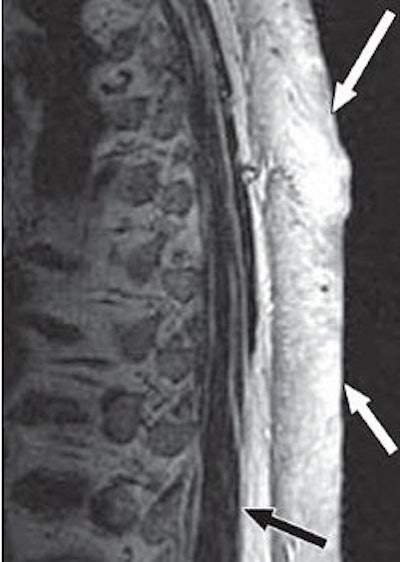

| A 65-year-old man with plaque-like diffuse neurofibroma. Above, sagittal T1-weighted MR image (TR/TE, 500/16) shows thick plaque-like diffuse neurofibroma involving skin and subcutaneous tissues of back. Deep aspect (black arrow) of mass is well-defined, and deeper subcutaneous tissues are uninvolved. Small flow voids (white arrows) reflect prominent internal vascularity. Below, sagittal T2-weighted MR image (3,200/104) shows diffuse neurofibroma (white arrows) that is markedly hyperintense in relation to muscle (black arrow). |

![]() |